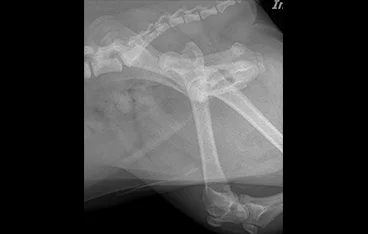

골절

골절 수복(screw, plate, k-wire, pin 등)

• 복합골절

• 최소침습 골절수술